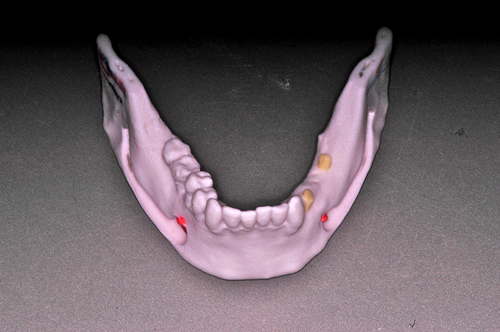

Palabras Clave: ELG: Estereolitográfico OH: Oclusión Habitual ORC: Oclusión en Relación Céntrica Paciente de 35 años de edad ,sexo masculino que lo derivan para implantar el tercer cuadrante. A la auscultación presenta ruidos articulares de tipo chasquido que remiten temporalmente luego de limitación de apertura bucal y maniobras quinesiológicas distractoras. También se observan recidivas de caries en algunos empastes y falta de disclusión canina de ambos lados. Se estudia el caso desde un punto de vista clínico, scanografico mediante Dentascan y tridimensional mediante montaje en articulador. A partir del scanner se obtienen datos para confeccionar modelo estereolitográfico (ELG),operar en el y construir férula quirúrgica dento-muco soportada. Habitualmente se procede directamente a implantar, dado que ese era el requerimiento del profesional derivante y el deseo del enfermo. Sin embargo, esa actitud enmascararía otro tipo de problemas que la boca presenta. Se consulta al odontólogo derivante, y coincide con mi opinión acerca de que si solo se lo implanta, sin corregir la posición mandibular, la situación de las ATMs, los empastes sin anatomía y la falta de disclusiones, el resultado final no será el deseado y su eficacia masticatoria no funcionará optimamente. Consultado el paciente coincide y acepta ese concepto y entonces procedemos a confeccionar un Jig de Lucia a partir del montaje de estudio, y lo dejamos puesto en boca toda la noche anterior a la consulta, para proceder a realizar un ajuste oclusal al día siguiente sin engramas anteriores, lo que facilita no tener que relajar nuevamente con laminillas de Long. En esta etapa pierde el implante correspondiente a la pieza 4.7 que traía en boca. Estabilizado el sistema, procedemos a la parte quirúrgica, comenzando por instalar la férula, retirar opérculos gingivales mediante bisturí circular, fresado óseo e instalación de implantes ,toma de impresión a cubeta fenestrada (pegando con metacrilato sin cambios dimensionales, los transfers a la cubeta especialmente diseñada.(1º método de pasividad protética utilizado), e instalación de tornillos de cicatrización. Inmediatamente de retirada la cubeta de boca y colocadas las réplicas de los implantes, procedemos a ferulizar los “ápices” de las réplicas para que no sufran movimientos durante el llenado de la impresión.(2º método de pasividad protética utilizado). Controlamos radiograficamente Tres meses después, procedemos a tomar nuevos registros de arco facial, registros intermaxilares en Oclusión en Relación céntrica, montaje de los modelos obtenidos intra operatoriamente y confección de un conjunto de cuatro coronas provisionales de metacrilato en el sector implantado y las correspondientes al maxilar superior. Verificada la perfecta función de todos los componentes, ausencia de todo tipo de síntoma y comprobada la paz en todo el sistema, procedemos tiempo después a confeccionar las fundas definitivas, que constituyen el “cerrojo” de la dinámica del mismo. Por último, corroboramos la oclusión fundamentalmente en lo que hace a la: